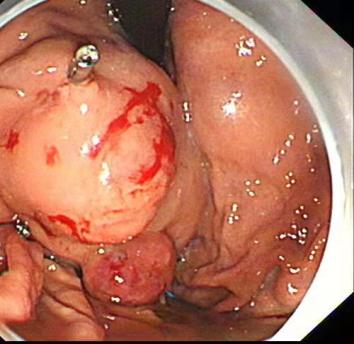

⑤ESD

随着内镜微创技术的发展,越来越多的早期消化道癌、癌前病变及胃肠黏膜下疾病可完全在内镜下予以切除,免除了更大的手术创伤,这就是内镜黏膜下剥离术ESD(endoscopic submucosal dissecfion)

该治疗具有不改变消化道解剖结构、不开刀、体表无创口、创伤、出血少、恢复快等优势,是近年来国际、国内最新兴起的内窥镜下微创治疗手段之一,适用于食管、胃、十二指肠等上消化道及结、直肠的黏膜下良性肿瘤、黏膜的早期癌变以及具有癌变倾向病变的切除治疗。因其特殊的微创优势,得到广大医生及患者的推崇,是消化道黏膜及黏膜下病变治疗的新兴发展趋势。我中心已经开展该项技术,技术成熟,并还开展了经口内镜下肌切开术POEM、内镜经粘膜下隧道肿瘤切除术STER、粘膜下隧道内镜剥离术ESTD,术后病人随访,恢复良好。

Ⅳ、ESTD治疗多灶性复发型食管早癌

Ⅴ、ESTD治疗超低位大面积直肠早癌

Ⅵ、STER治疗食管固有肌层肿瘤